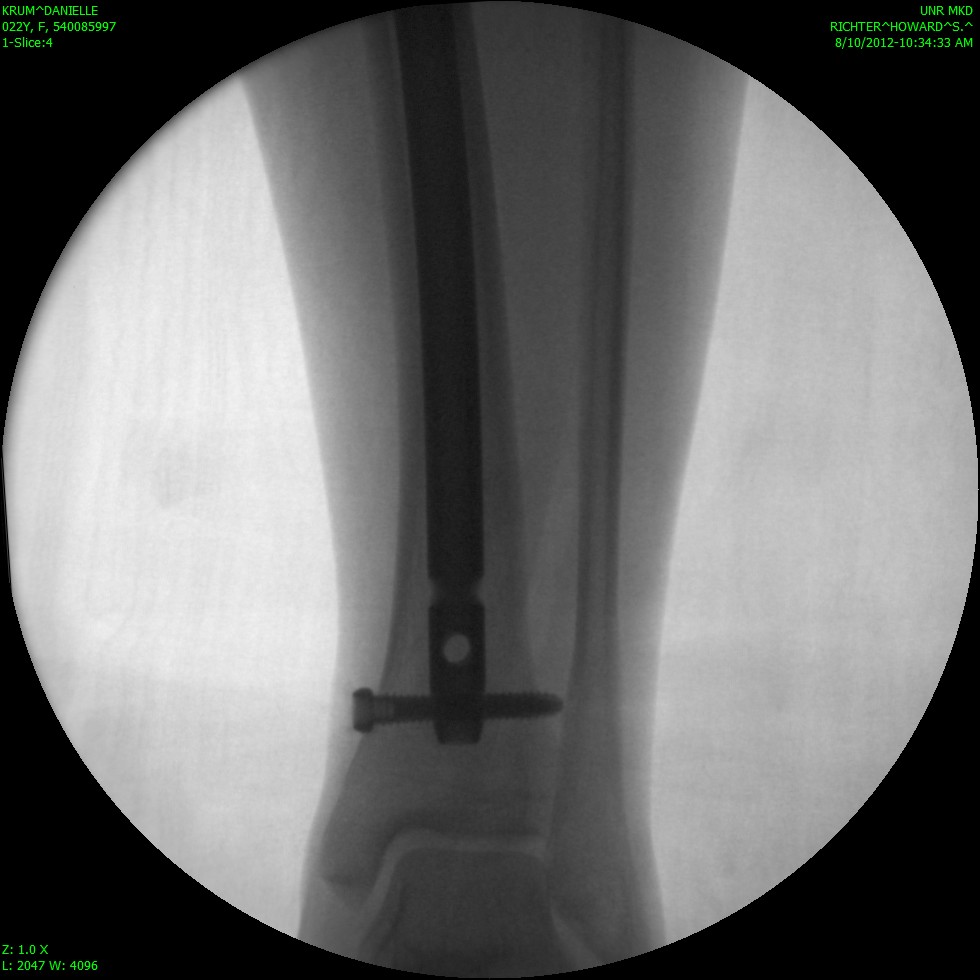

Sorry that I have been MIA for so long! I actually broke my leg on August 9th… I fractured my tibia (the big weight bearing bone in your shin) all the way through. I had the option to be in a full length cast (from my hip to my toes) for 8 weeks, or to have surgery and a rod placed so that I can walk on my leg. I chose to have surgery and now I am just going through recovery. I am working on teaching myself how to walk normal with that leg again. I am happy to be up and moving and not in a cast, but its definitely not a fun process. I have new crafts to put up soon! Some darling candy corns and a pumpkin set for the porch! I will work on getting those posted as soon as I can.

Here are some awesome pictures of my broken leg!